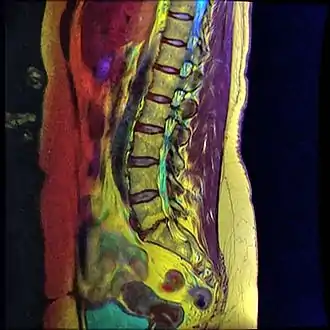

Grade 1 retrolistheses of C3 on C4 and C4 on C5